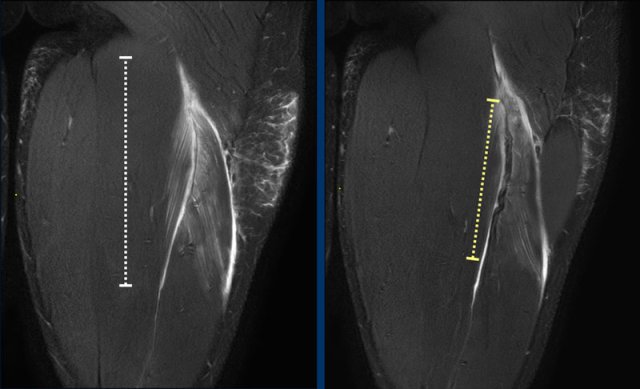

Total length of the edema is noted (white dotted line). Now take a closer look at the tendon (yellow dotted line) and continue reading.

Length of tendon distortion

When the tendon looks normal, straining is probable low grade.

Tendon thickening, tendon waviness, high signal of the tendon can all be signs of higher grade straining.

Case 1: normal tendon.

Case 2 slightly thickening and wavy aspect of a short length of the tendon.

Case 3: obvious thickening and waviness

All these signs have to be described in your report.

Total length of the distorted tendon is noted.

Both length of edema and distorted tendon are measured and noted in the report.

In this case, biceps femoris tendon injury was classified as grade 3 partial injury, since the length of the edema is > 15cm (white dotted line) and the length of the distorted tendon is > 5cm (yellow dotted line).

Two more cases to demonstrate this classification.

A muscle edema 5-10cm (white dotted line) present at the MTJ without architectural distortion of the tendon, classified as BAMIC 2b.

B muscle edema >15cm (white dotted line), at the MTJ / intramuscular tendon, tendon distortion > 5cm (yellow dotted line). The tendon shows disruption with loss of low signal intensity within the tendon along with a wavy appearance indicating focal loss of tension. BAMIC 3b/c.